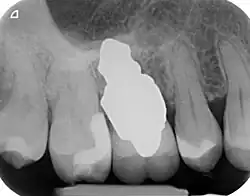

RAIs are custom made to perfectly fit the tooth socket of a specific patient immediately after tooth extraction. Therefore every implant is unique. As an optimised root-form it is much more than a simple 1:1 replica of a tooth. Since it exactly fills the gap left after the tooth is extracted, surgery is rarely needed. The implant can be produced from a copy of the extracted tooth, an impression of the tooth socket, or from a CT scan or CBCT scan.[7] The advantage of a CBCT scan is that the implant can be produced before extraction. With the former methods, it takes one or two days to fabricate an implant.

A root analogue implant can be fabricated from zirconium dioxide (zirconia) or titanium.[8] Successful titanium RAIs have been three-dimensionally printed as porous one-piece implants, using CAD software.[9] However, zirconia is the preferred material, because it is more esthetic in colour, with no grey discolouration visible through gums.[10][5]

- Natural form: a custom milled anatomic implant replicates the natural form of a tooth, so it simply fits into the tooth socket. Like the original tooth, a root analogue implant can have single- and multi-rooted forms.

- Esthetic: a ceramic RAI closely resembles a natural tooth in colour. Thus there is no discolouration through the gums, as is commonly seen with titanium implants.